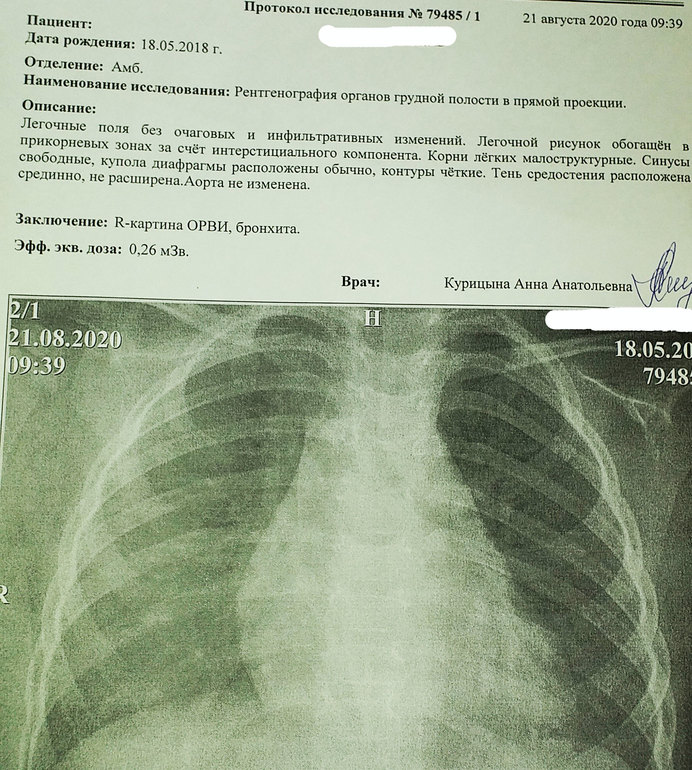

Сегодня сделали рентген, так как было подозрение на пневмонию. Сын еще кашляет, но кашель меньше, горло все так же красное.